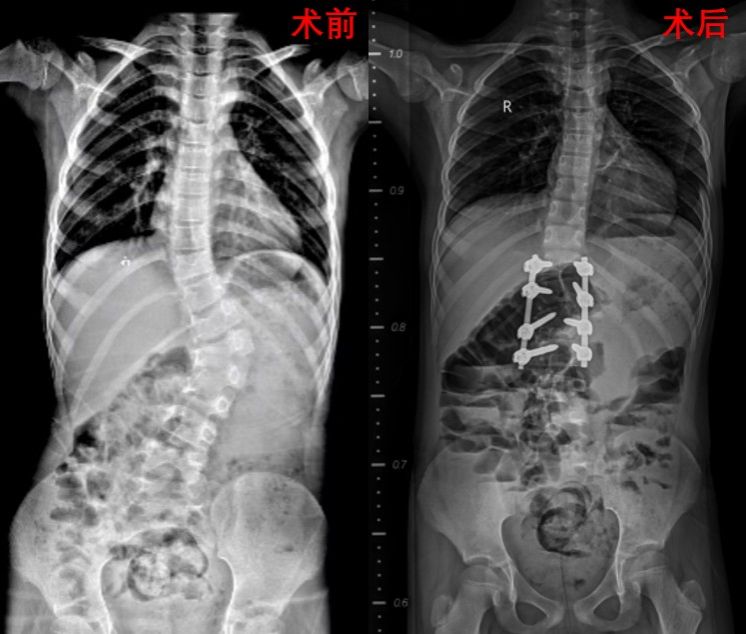

本次接受手术的两名患者均为7岁学龄期儿童,术前完善影像学检查提示分别为腰5和腰1半椎体畸形,脊柱侧凸Cobb角度分别达40°和58°,伴随明显躯干失衡。王栋主任团队通过脊柱全长X线、三维CT、MRI及神经电生理评估,为患者制定个体化3D打印模型及个性化手术方案,采用“后路脊柱侧凸截骨矫形+椎弓根螺钉固定+植骨融合术”,术中运用超声骨刀、术中神经监测等先进技术,在矫正畸形的同时最大限度保护脊髓功能。

手术过程由王栋主任主刀,分别在秦杰副主任医师、郭帅主治医师、郭秦规培医师以及张廷副主任医师、李京主治医师、刘亭规培医师的紧密配合下,由神经电生理监测团队、麻醉科全程护航,输血科保障血液供应。王栋主任表示:“青少年脊柱侧凸矫形是毫米级的精准手术,需在矫正畸形与保留脊柱生长潜能间取得平衡。"两例手术历时均控制在3小时内,出血量不足400ml,术后患者转入骨科加速康复(ERAS)病房,由护理团队实施精细化围术期管理和科室特色无陪护病房陪护团队的悉心呵护,两位患儿现均已在支具保护下下床活动。